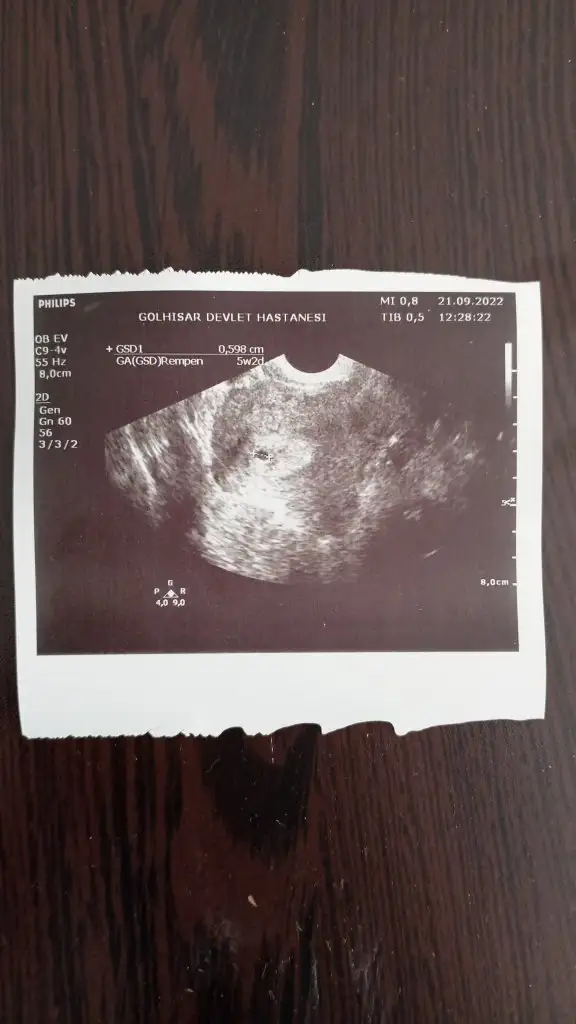

Merhabalar banada bakabilirmisiniz lütfen 🙏 5+2 karından